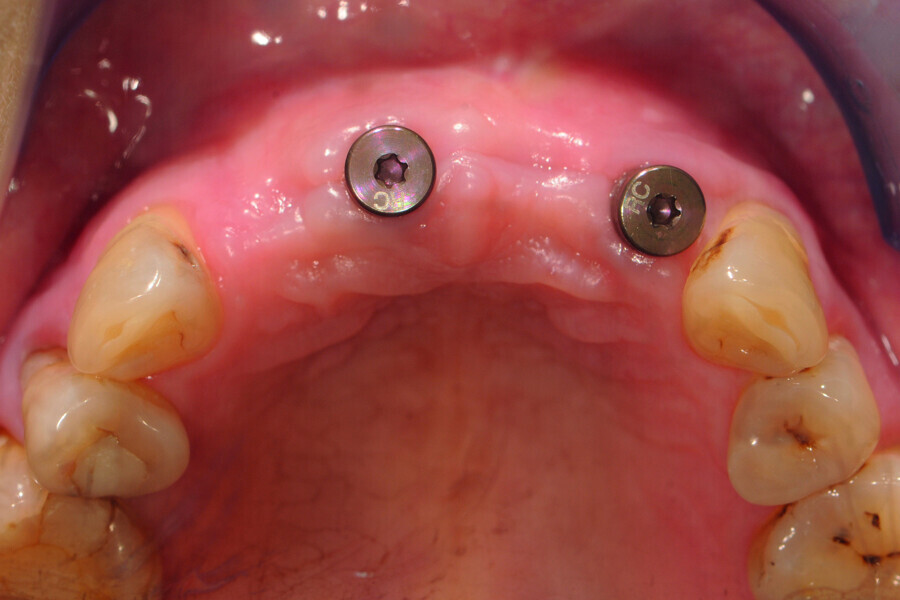

Fig. 2: Pre-op occlusal view of the anterior teeth.